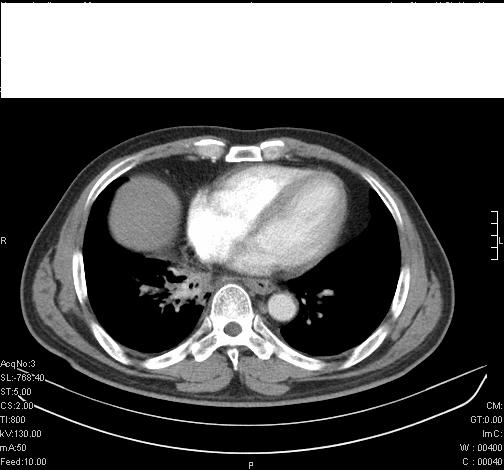

前几天,发了患者的平扫片,患者抗炎一周后增强扫描。右中叶病灶吸收明显,但下叶病灶未见明显吸收。右肺门可见结节影,看来凶多吉少

第18幅,好像不能简单用炎症解释,前几天我发平扫时,90%人支持肺癌,现在好像大家更倾向于炎症了,我觉得还是不能排除肺癌。

右肺下叶支气管壁不规则增厚,右肺下叶有斑片状影分布。考虑右肺中央型肺癌伴右肺下叶阻塞性改变。建议支纤镜检查。平扫比增强较好显示了病变情况。

右主支气管狭窄,管壁增厚。考虑右中心性肺ca伴阻塞性肺炎。

既然抗炎治疗有效,可继续治疗;右肺下叶支气管管腔狭窄,管壁增厚,右下肺见斑片状高密度影,右侧主支气管后见结节影(淋巴结?),肺癌不能排出。